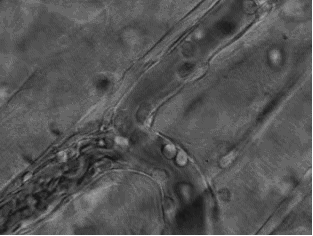

工作中的免疫细胞 免疫细胞既能抵抗、消灭入侵人体的病菌 又能清除自身衰残、癌变的细胞。 这张动图显示的是嗜酸性粒细胞 在趋化作用的“感知”下 逐渐聚集到一只秀丽隐杆线虫周围 并对它进行攻击的过程。 有“成千上万”的嗜酸粒细胞围聚在线虫周围, 就像一群蚂蚁,善打“包围战”。 这是中性粒细胞 追击金黄色葡萄球菌的一个过程。 免疫细胞捕捉细菌时超萌! 免疫细胞也可穿过血管壁奔赴“战场”, 向炎症和创伤组织处进军、围剿。  免疫系统与机体健康 免疫系统三大功能 01 免疫防御:识别和清除外来入侵的抗原,如病原微生物等,使人体免于病毒、细菌、污染物质及疾病的攻击。 免疫监视:识别和清除体内发生突变的肿瘤细胞、衰老细胞、死亡细胞或其他有害的成分,防止肿瘤的发生。 02 自身稳定:通过自身免疫耐受和免疫调节使免疫系统内环境保持稳定。 乘坐公共交通工具时,应全程佩戴口罩,注意与他人保持距离。随时保持手卫生,减少接触交通工具上的公共物品。 当人体处于亚健康状态时,这三方面的功能都会受到不同的影响,表现为整个免疫系统功能受损,出现一系列与免疫系统相关的临床表现或疾病,而不是仅在某一个疾病中孤立的异常表现。  免疫细胞与衰老 人体免疫功能随着年龄增长逐渐衰老退化,人体的免疫力在青年时期达到巅峰,之后逐渐减弱,40岁以后会加速衰退,到了70岁,更是只剩下巅峰期的1/10。 免疫细胞功能减退是衰老的最明显特征之一。人体衰老过程中,免疫细胞的构成发生了变化:T、B细胞绝对值明显减少,亚群也有变化,其增殖能力减弱。免疫细胞随着衰老各种功能发生很大改变,出现对抗原的精细识别能力下降、精确调控功能减弱,以及免疫应答紊乱、低效和无效,使免疫系统的三大功能失调或减弱,最终导致癌症、感染性疾病、自身免疫性疾病的发生率明显增加。  免疫细胞的应用 1、预防肿瘤 诱发癌症的因素有很多,而处在同样致癌环境中的人,仅有少数会患上癌症。这其中一个最重要的原因就在于,个体对癌细胞的免疫功能强弱不同,免疫功能越低,癌症的发病风险越高。 正常人体内每天都有上百个细胞发生基因突变,随着年龄的增长,基因突变现象甚至会增加到每天3000次以上。免疫功能正常时,这些突变细胞会被免疫细胞及时清除,不会对人体产生危害。当人体免疫力低下时,这些突变细胞就可能发展为肿瘤。老年人免疫力低下,所以癌症发病率远高于年轻人。 2、降低心脑血管疾病发病风险 心脑血管疾病发生的根本原因是血管内皮细胞受损。当血管的内皮细胞受损脱落或功能缺陷时,不能为血液流动提供光滑的平面和分泌多种生物活性物质,如:一氧化氮、前列环素2等,导致血管中的血小板和交联大分子在血管壁上淤积,形成突出于官腔的粥样斑块,使管腔狭窄,血液流动受阻。 免疫细胞能够清除血管内堆积的血小板和交联大分子,降低血脂、血粘稠度,恢复血管的顺应性,改善血管内环境,增强血管功能。从而有效预防和治疗高血压、血栓、冠状动脉粥样硬化等心脑血管疾病。 3、抗衰老 免疫细胞能够高效识别并清除体内衰老、凋亡的细胞,对机体起着清道夫的作用,从而维持机体内环境的稳定,改善各类细胞的生存环境,减少衰老细胞的危害,直接防止衰老相关疾病的发生。 同时,免疫细胞本身可以分泌多种细胞因子,增强活化机体免疫系统,调节免疫平衡,促进身体器官新生细胞产生,提升精力体力,使机体保持年轻状态。 4、改善亚健康 世界上最好的健康卫士就是自身的免疫细胞。人体90%的疾病与免疫失衡有关,通常病毒和细菌只能在免疫力低下的情况时才导致发病。亚健康人群,通过回输免疫细胞能将体内的“异己”和“非己”成分,包括病毒、细菌等致病微生物和体内产生的突变细胞及引起变态反应的物质识别出来,并加以吞噬、消灭和清除。从而维持人体内环境的稳定,改善各类细胞的生存环境,达到提升免疫力,降低发病率,消除亚健康的疗效。  免疫细胞疗法 人体的细胞每天分裂都会有一部分出错,正常的免疫系统能及时清除绝大多数错误分裂的细胞,得通过爱护保养自身的免疫系统,规律生活,均衡饮食,才能解决。 免疫细胞疗法通过诱导激活自体免疫细胞并回输到体内,可以提高、平衡机体免疫能力,达到有效抵抗衰老进程,消除亚健康,恢复健康状态,使与免疫相关的疾病减轻甚至治愈,减少常见病发生,甚至能够尽可能的预防癌症发生的风险。 补充健康细胞、修复受损细胞、替换衰老感染细胞,以自身免疫细胞守卫机体健康,达成健康人生!  如何成为“长胜将军”